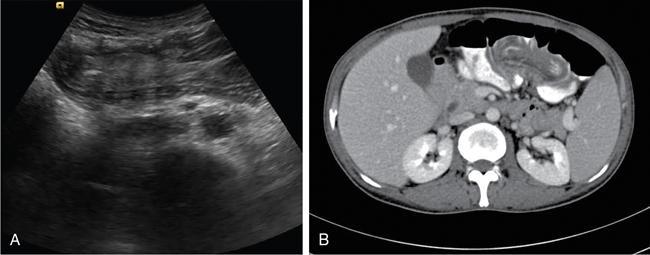

Ultrasonography (USG)